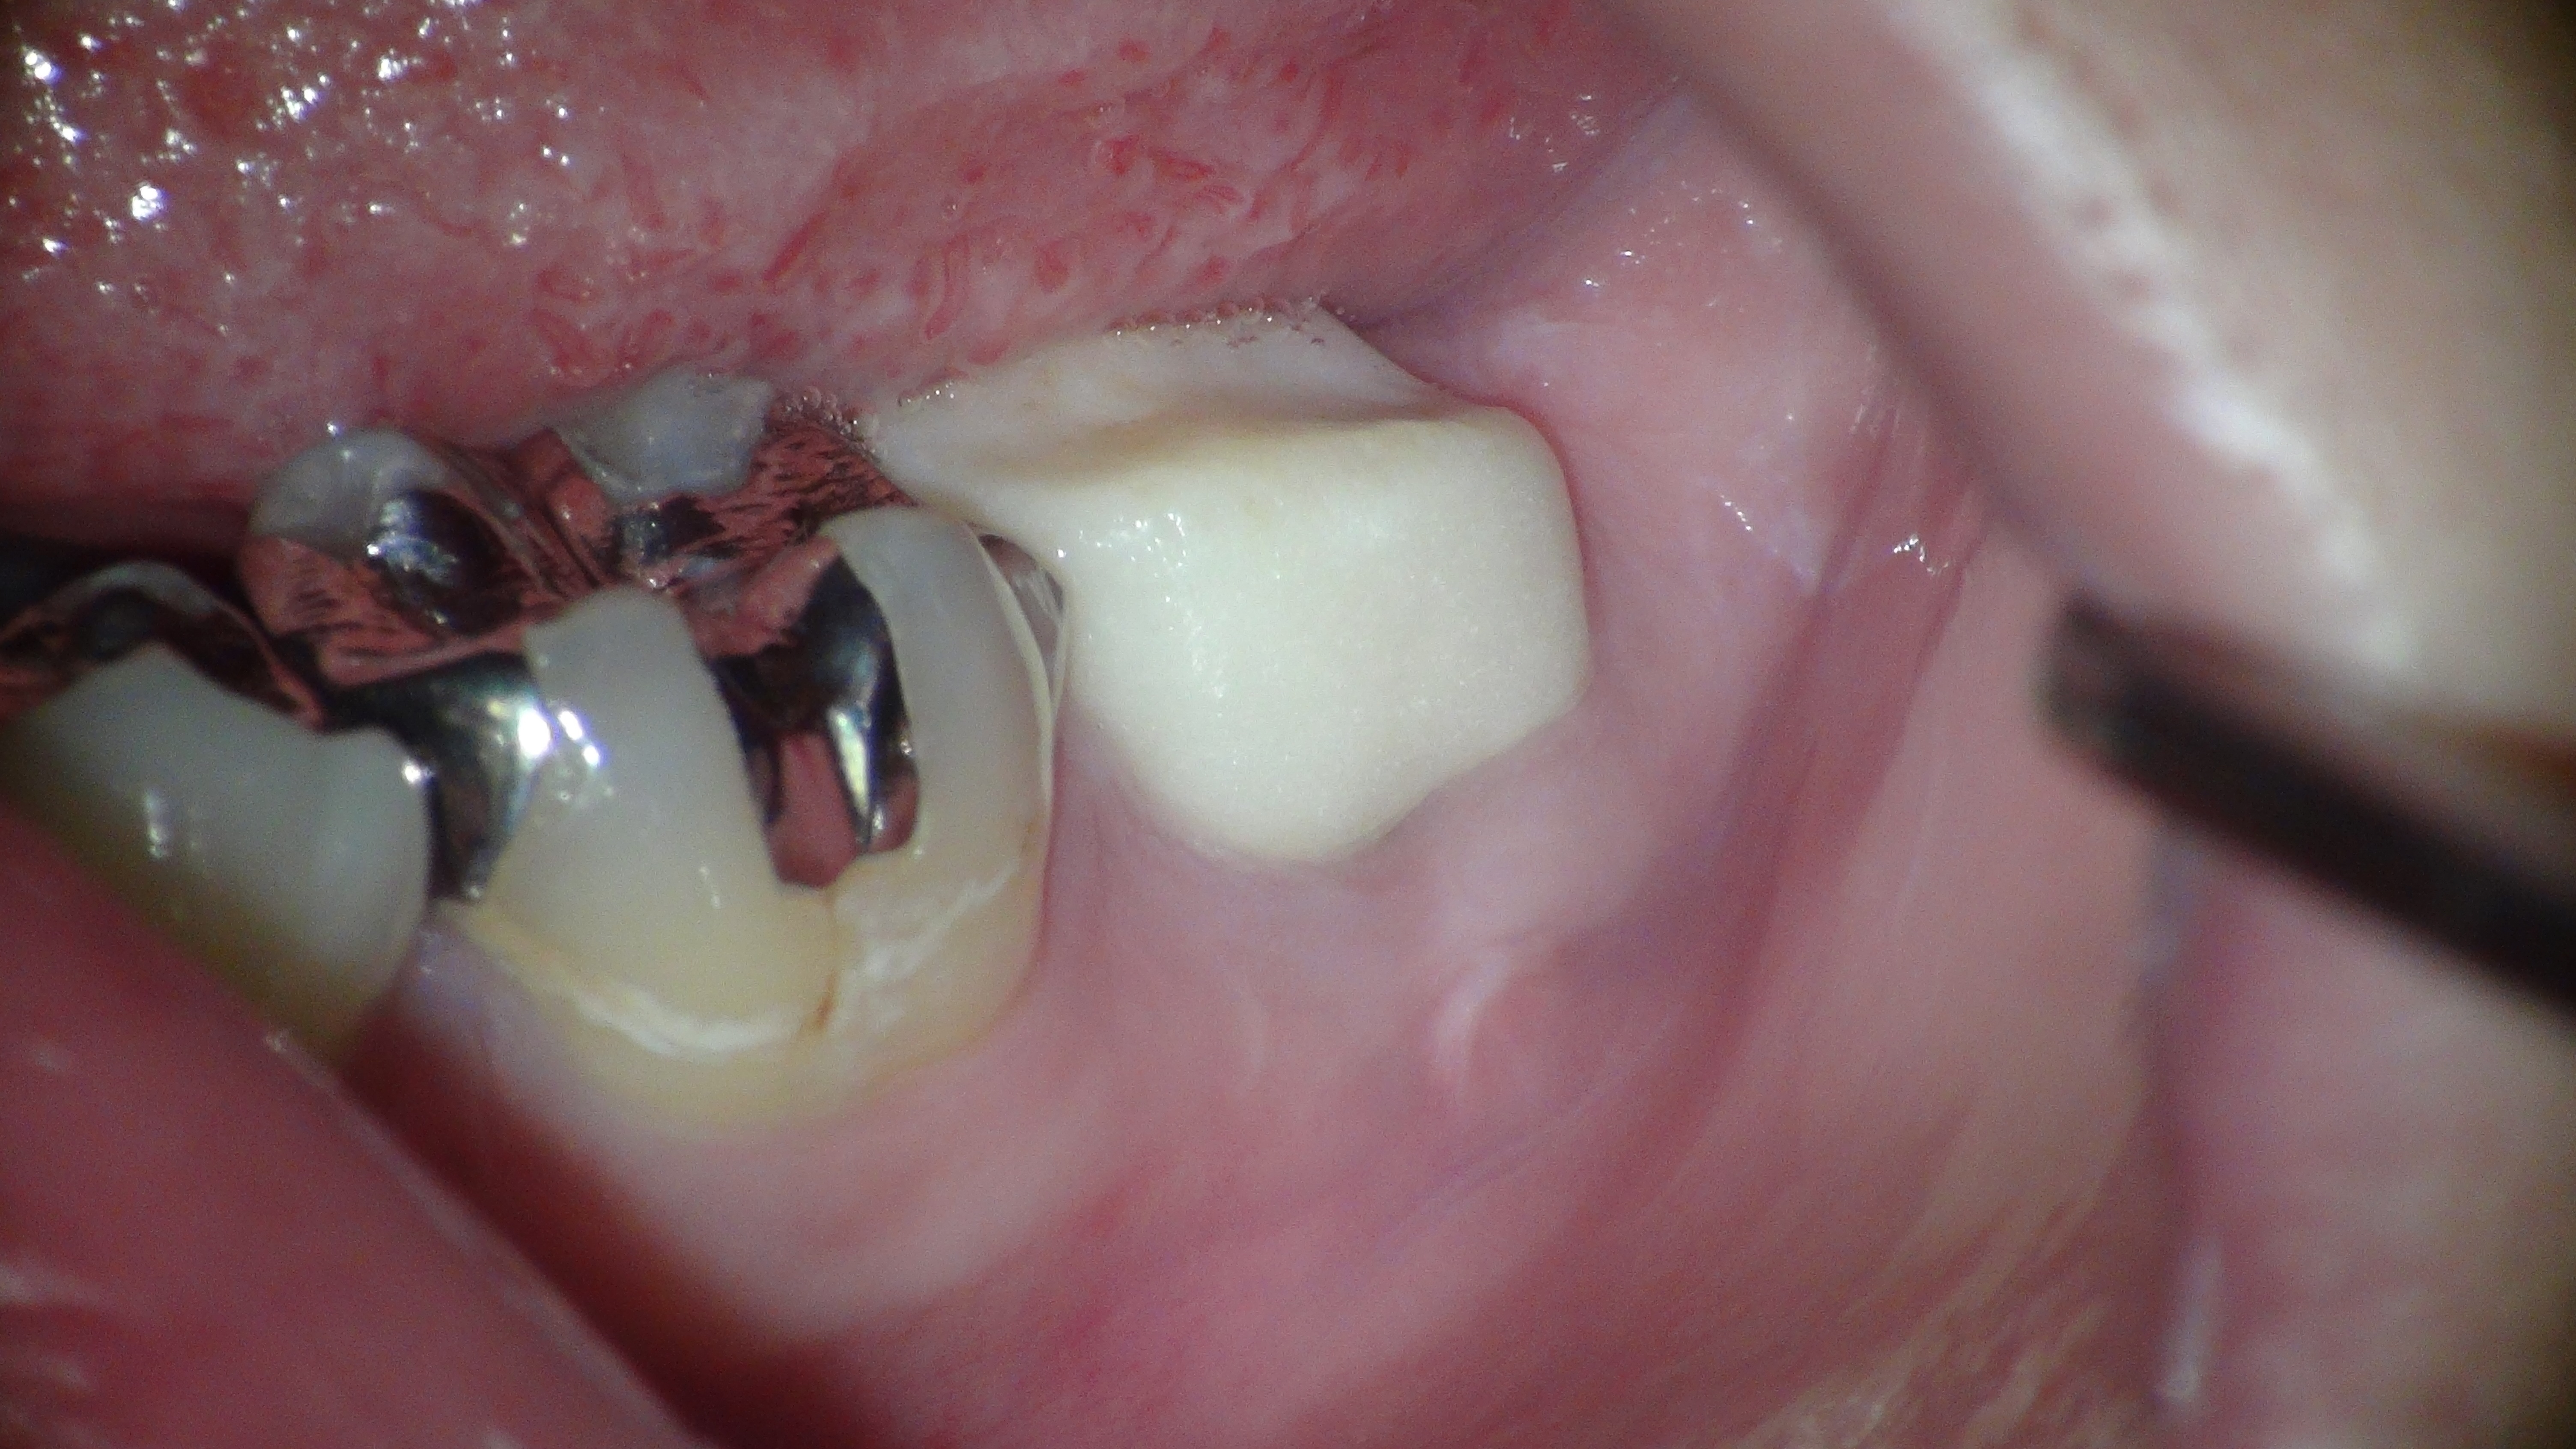

根の治療が終わった後、症状も特にないことから新しい土台と仮歯を入れて当クリニックの治療は終了となりました。

↑当クリニック治療終了時